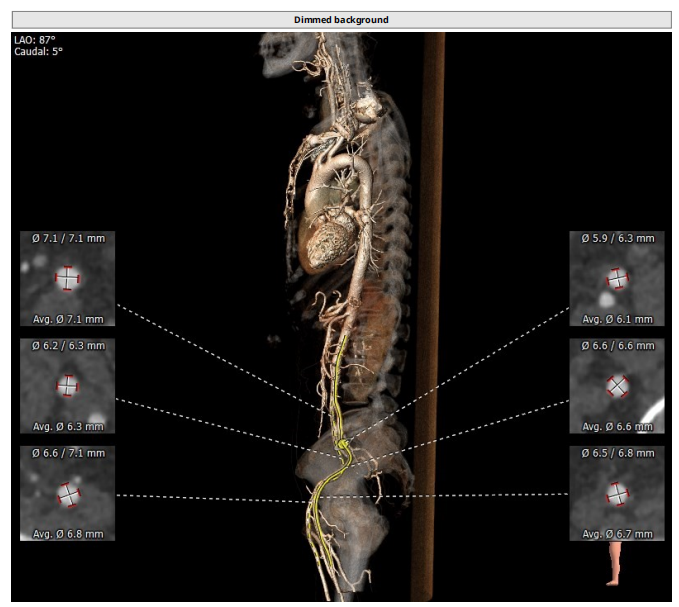

瓣环:16.9mm;左室流出道:16.7mm

STJ:23.9mm;升主动脉:31.4mm

工作体位:LAO:12°CRA:5° ;左冠切线位:LAO:26° CRA:19°

右股为主入路

患者为三叶瓣,左右、右无疑似粘连,瓣叶明显增厚,轻度钙化。右冠高度10.9mm,左冠高度9.5mm,冠脉高度均较低。法式窦小,心脏角度不大,左室大小可,升主动脉未见明显增宽,病人整体结构小,瓣环仅有16.9mm,左室流出道16.7mm,窦管结合部23.9mm,升主动脉31.4mm。选择右股作为主入路。